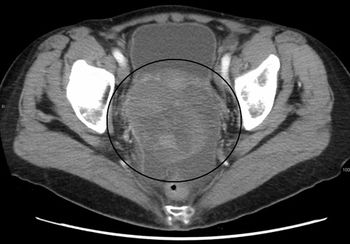

A novel therapy has shown activity in the treatment of difficult-to-treat, advanced, platinum-resistant ovarian cancer. The drug, DMUC5754A, is part of a new class of drugs called antibody-drug conjugates.